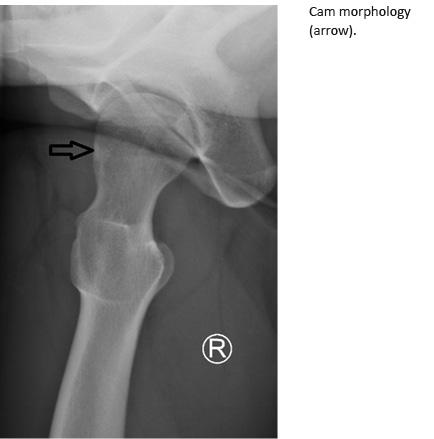

3. X-ray examination of the hip using the antero-posterior view showing the morphology of the cam-

type (alpha-angle > 55 degrees on the head-neck junction), pincer type (cross-over sign at the acetabular rim) or mixed type